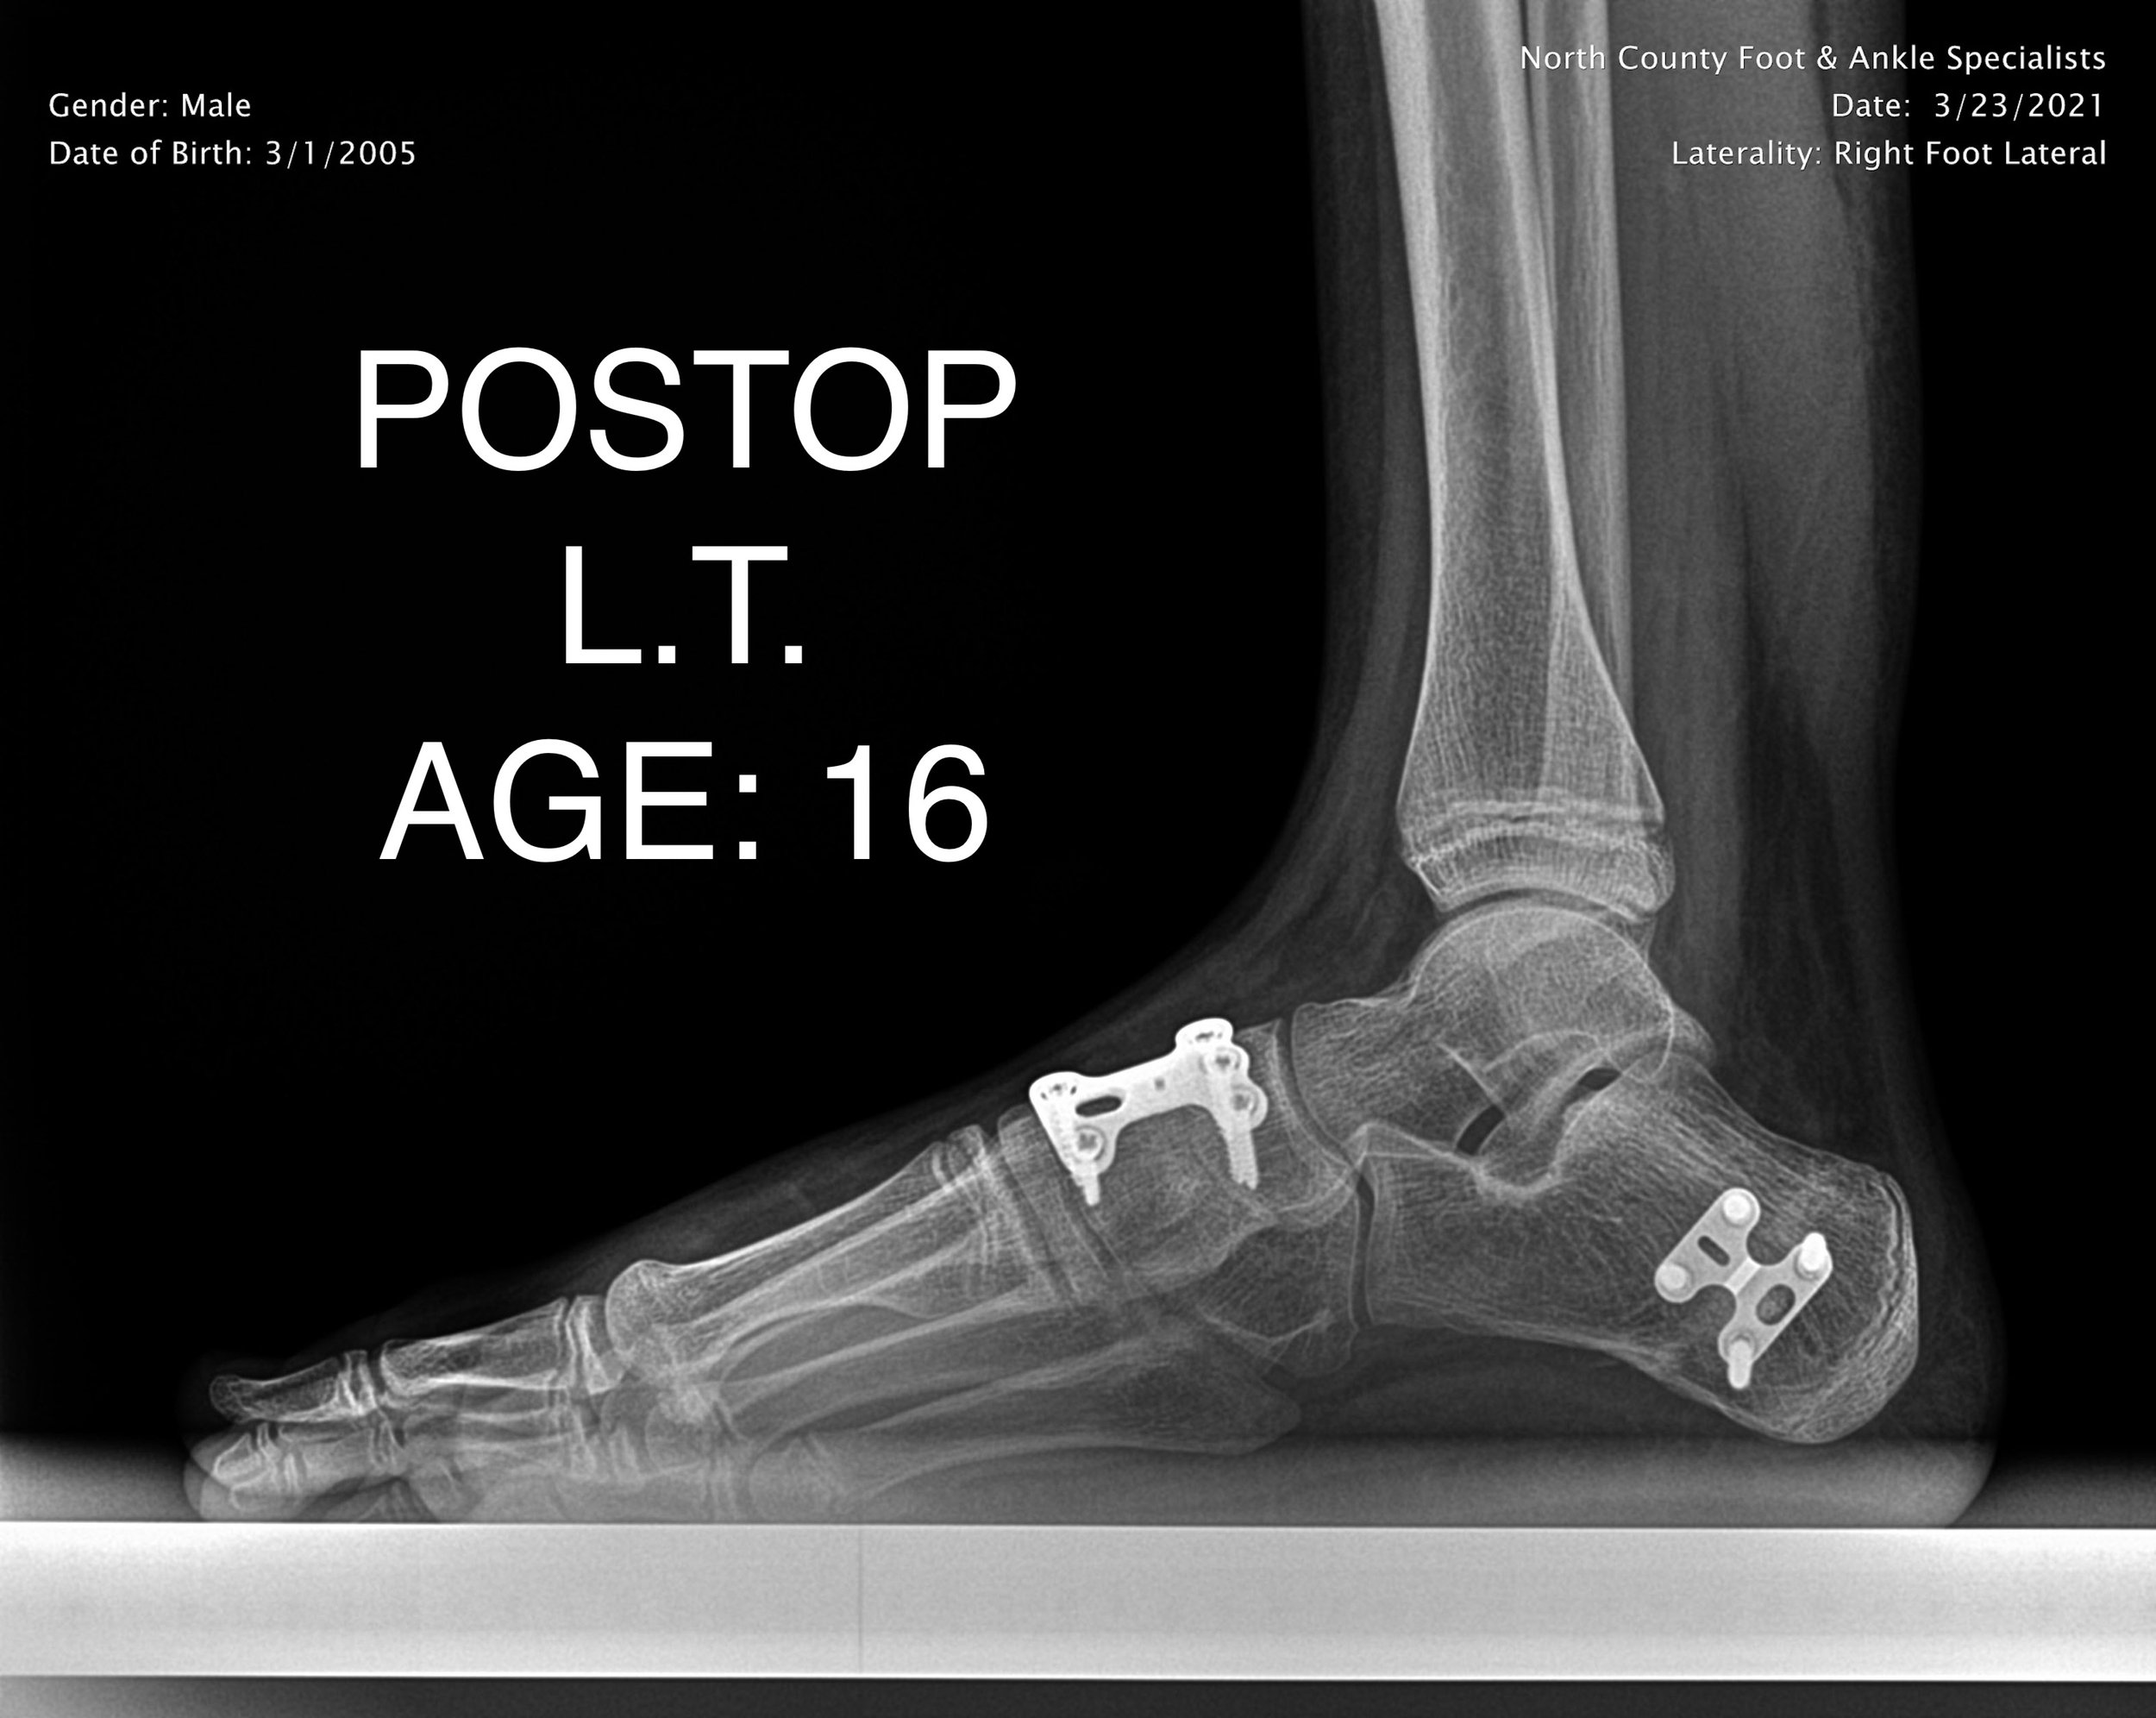

PEDIATRIC FLAT FOOT